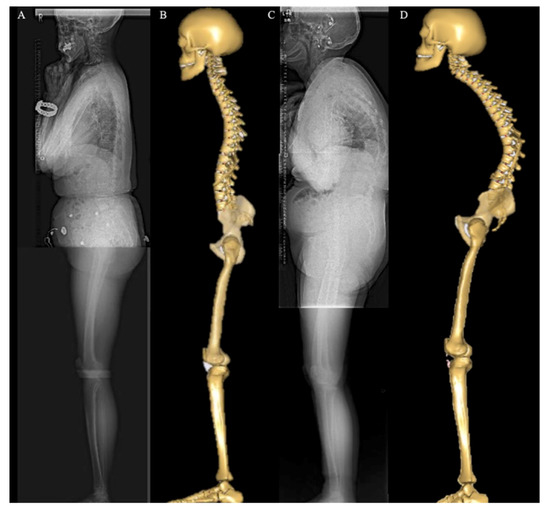

2.2. Image Acquisition and Anatomical Parameters Extraction